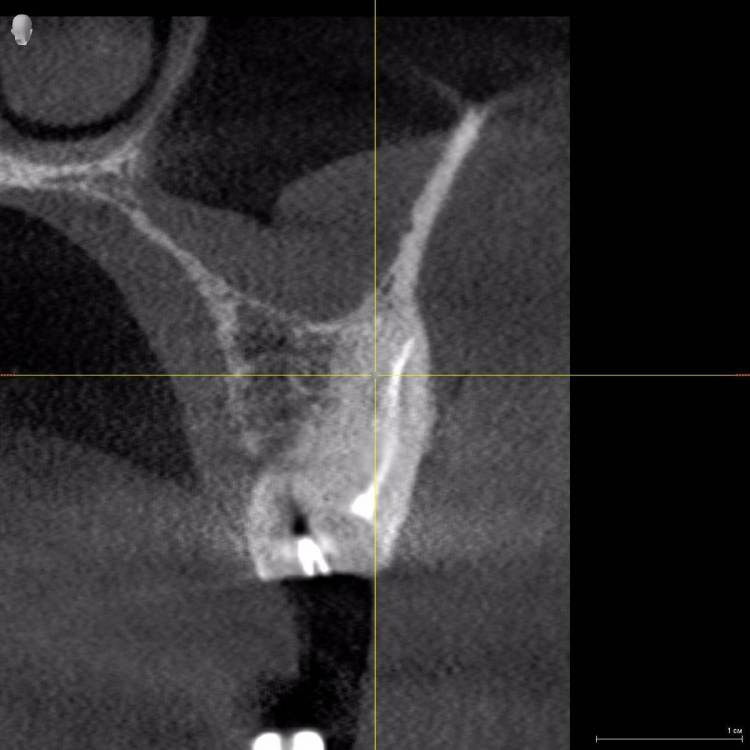

Алексей82 Опубликовано 10 марта, 2022 Автор Поделиться Опубликовано 10 марта, 2022 Здравствуйте. Вот ссылка на КТ. Посмотрите пожалуйста. Или может надо было скрин сделать чегото. https://dropmefiles.com/zxr3f Ссылка на комментарий

wladdX Опубликовано 10 марта, 2022 Поделиться Опубликовано 10 марта, 2022 (изменено) Попробовать поработать в корневых каналах можно, насколько это будет успешно, сказать невозможно. Изменено 10 марта, 2022 пользователем wladdX 1 1 Ссылка на комментарий